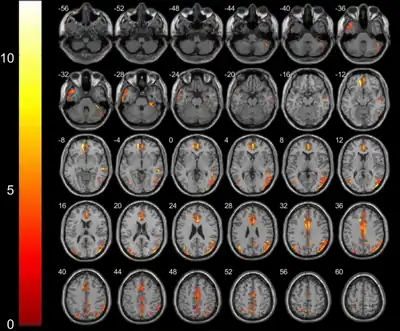

| This 16th-century painting by Flemish artist Pieter Bruegel the Elder is one of the oldest known depictions of the facial dystonia associated with this syndrome. | |